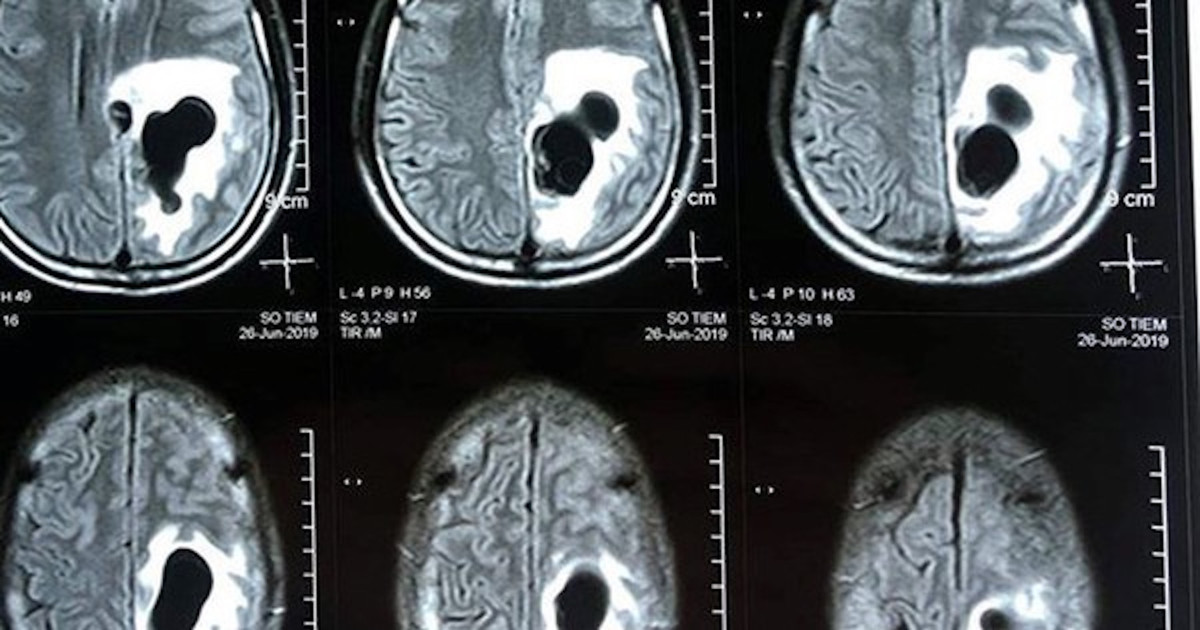

TS.BS Trần Huy Thọ, Phó giám đốc Bệnh viện Đặng Văn Ngữ cho biết, kết quả xét nghiệm ELISA của bệnh nhân dương tính với ấu trùng sán dây lợn. Chụp cộng hưởng từ sọ não thấy khối tổn thương ký sinh tại vùng não của anh N do ấu trùng sán dây lợn.

Não: Não là vị trí thường gặp nhất. Ấu trùng sán lợn cư trú trong hệ thần kinh trung ương, từ 60 - 96%. Những nang ở não gây bởi nhóm bệnh thần kinh như động kinh, tăng áp lực sọ não, viêm não, rối loạn tâm thần, viêm màng não, rối loạn chức năng thần kinh và thể phối hợp.

Các biểu hiện thường gặp: Nhức đầu 48,4%, động kinh 6,2%, rối loạn tâm thần 5,2%, rối loạn thị giác 15,6%, suy nhược cơ thể - giảm trí nhớ 28,1%, co giật cơ 34,3%.